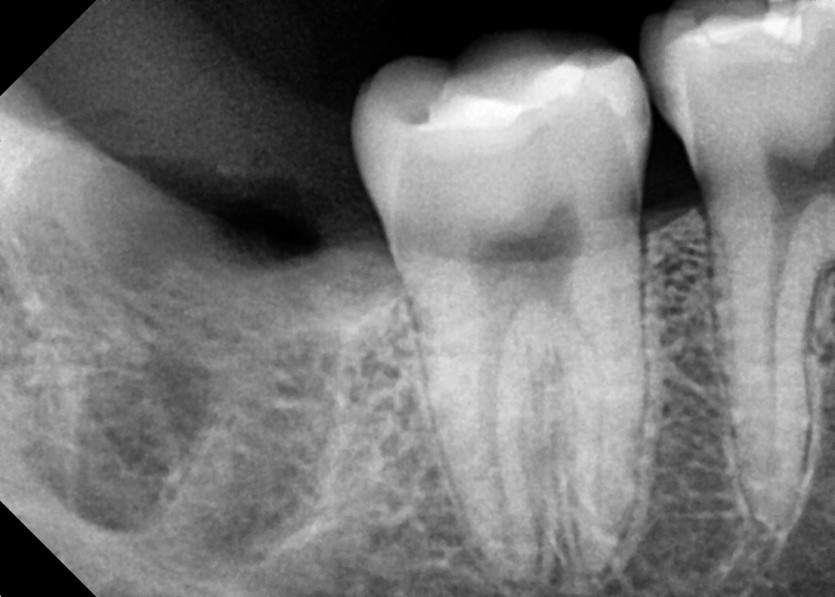

#48 사랑니 발치

구강 외과 전문의가 당일 발치했습니다.